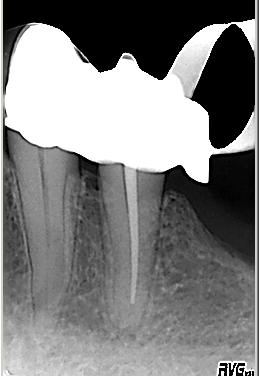

Distalexzentische Aufnahme mit zweitem Parodontalspalt im November 2002 wegen Schmerzen